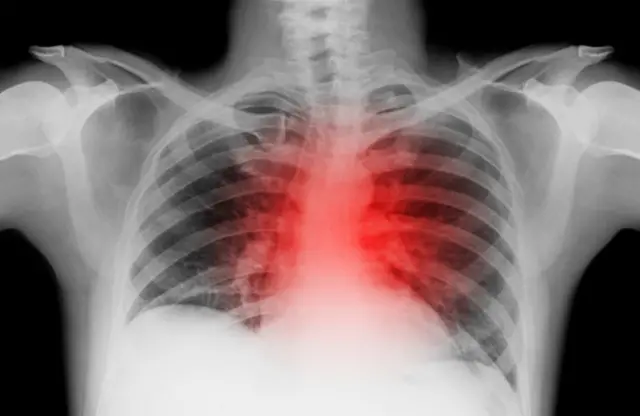

छातीत दुखू लागल्याने रुग्णालयात दाखल

येथील एम. पी. शाह वैद्यकीय रुग्णालयाच्या अधिष्ठाता (डीन) डॉ. नंदिनी देसाई म्हणाल्या, “मंगळवारी पहाटे 4 वाजता डॉ. गांधी यांनी छातीत दुखत असल्याबाबत तक्रार केली. त्यानंतर ते स्वतः जिथे प्रॅक्टिस करतात त्याच खासगी रुग्णालयात त्यांना नेण्यात आलं.

कार्डिओग्रामनंतर त्यांच्यावर अॅसिडिटीसंदर्भात उपचार करण्यात आले. उपचारानंतर डॉ. गौरव यांना बरंही वाटलं. त्यामुळे त्यांना डिस्चार्जही देण्यात आला.

गांधी यांच्या कुटुंबीयांच्या माहितीनुसार, उपचार घेऊन डॉ. गौरव घरी परतले. पण दोन तासांनी ते त्यांच्या बाथरूमजवळ खाली कोसळले. त्यामुळे त्यांना तत्काळ रुग्णालयाच्या इमर्जन्सी विभागात नेण्यात आलं. पण तिथे नेण्यापूर्वीच त्यांचा मृत्यू झाल्याचं डॉक्टरांनी सांगितलं.

याबाबत बोलताना डॉ. देसाई म्हणाले, “रुग्णालयात पोहोचल्यापूर्वीच त्यांचा मृत्यू झाला होता. त्यांचं शवविच्छेदन करण्यात आले असून त्याचे अहवाल येणं बाकी आहे. परंतु, प्राथमिक निरीक्षणावरून असं दिसतं की डॉ. गांधींना हृदयविकाराचा झटका आला होता.”